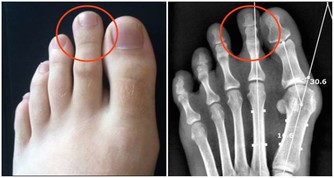

3、核桃——可秀甲

核桃中含有豐富的生長素,能使指甲堅固不易開裂同時核桃中富含植物蛋白,能促進指甲的生長。常吃核桃,有助於指甲的秀韌。